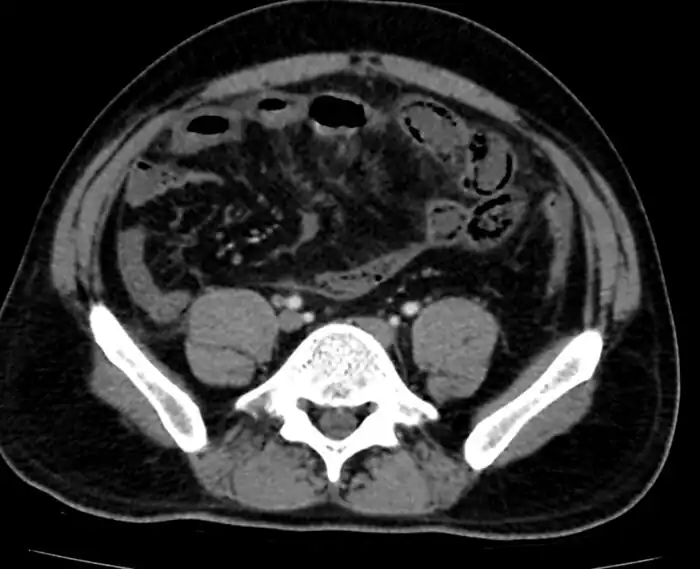

Mesenteric ischemia/CT image

Mesenteric ischemia